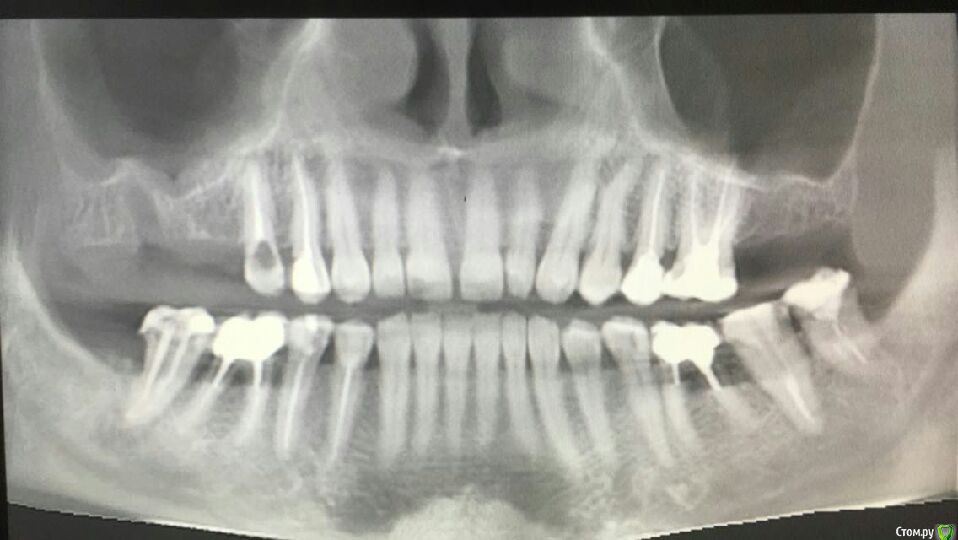

Musya31 Опубликовано 23 января, 2017 Поделиться Опубликовано 23 января, 2017 (изменено) Верх справа. Не помню, чтобы удаляла 8-ку. Это сидит видимо давно. Долго разбираюсь с болями в правой части лица, челюсти. Может быть причина здесь? Нужно удалять, как считаете? И трудным ли будет удаление? Ну и до кучи: нижняя справа семерка. Можно ли попытаться спасти? От нее тоже может болеть? Всем спасибо! Изменено 23 января, 2017 пользователем Musya31 Ссылка на комментарий

Musya31 Опубликовано 23 января, 2017 Автор Поделиться Опубликовано 23 января, 2017 (изменено) В 5-ке временная пломба, поэтому пусто Изменено 23 января, 2017 пользователем Musya31 Ссылка на комментарий